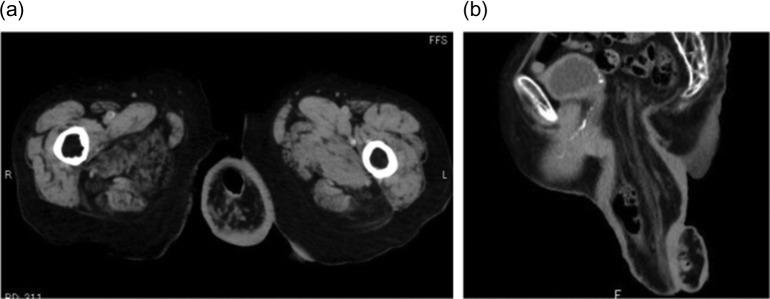

The guideline for the treatment of rectal prolapse recommends that surgeons select appropriate surgical procedures individually based on each patient's overall status. However, in cases of irreducible or incarcerated rectal prolapse, surgical options are quite limited. Here we present a case of an elderly woman with massive chronic irreducible rectal prolapse. An 87-year-old woman presented to our hospital with a complaint of massive rectal prolapse. The prolapsed rectum was over 20 cm long, and completely irreducible. She underwent perineal rectosigmoidectomy with levatorplasty known as Altemeier's procedure. More than 30 cm of rectosigmoid colon was resected. After the operation, rectal prolapse was resolved completely. Her postoperative course was uneventful, and her quality of life and bowel movements improved. She has since been healthy without recurrence for over 2 years. Altemeier's procedure is applicable even in cases of irreducible rectal prolapse and features acceptable safety and a satisfactory outcome.

https://cdn.ncbi.nlm.nih.gov/pmc/blobs/704c/5888366/5fefdbe2f5b0/rjy064f01.jpg